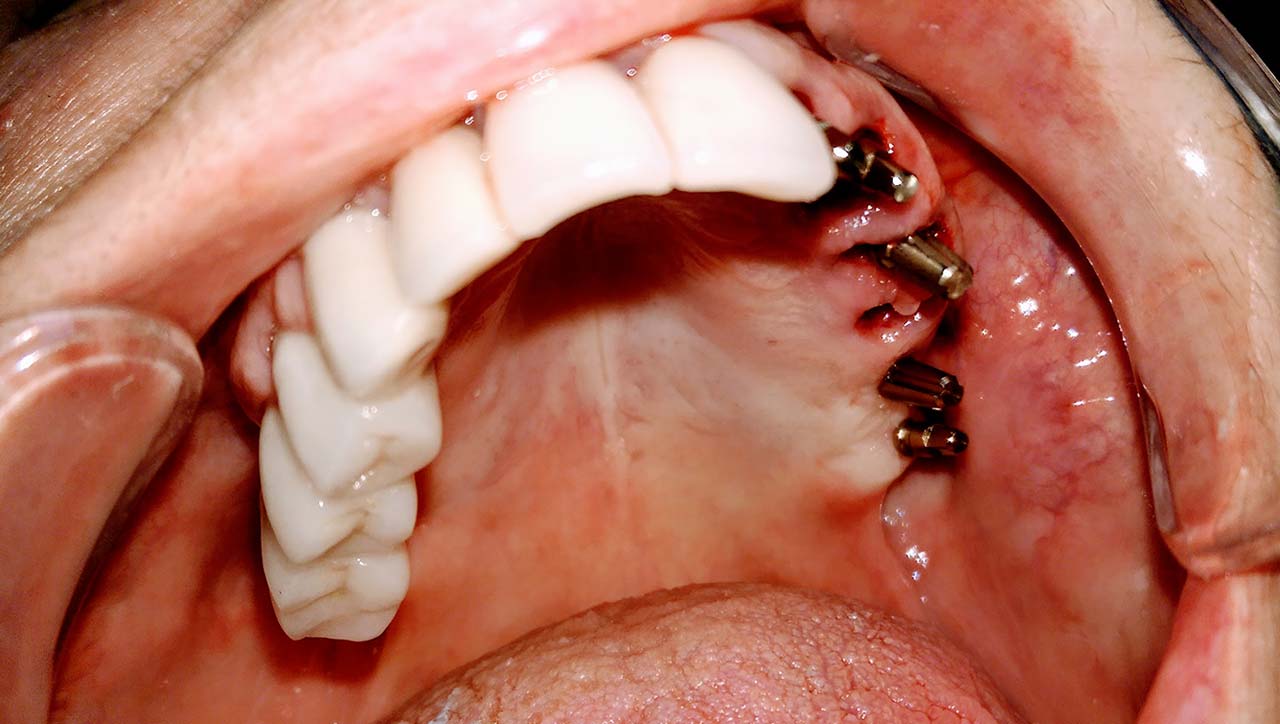

Alsó állcsont teljes rehabilitációja 72 óra alatt, azonnal terhelhető implantátumokkal súlyos paradontitisben szenvedő dohányzó páciens esetében. Az alsó állcsont fogai mind mozogtak az előrehaladott fogágypusztulás miatt.

A fogakat eltávolítottuk, a gyulladt, fertőzött csontot kitakarítottuk, kifertőtlenítettük, majd azonnal implantáltunk.

Svájci, IHDE márkájú, azonnal terhelhető implantátumokat helyzetünk be, és ezekre harmadnapra rögzített, hosszútávú, fémvázas, esztétikus műanyaggal leplezett hidat ragasztottunk be.

Ezt az ideiglenes hidat a sebek gyógyulása miatt használjuk, de tartóssága miatt véglegesként is használható.

A legtöbb esetben, ahogy itt is, 6 hónap múlva porcelán hídra cseréljük, a teljes gyógyulás után.